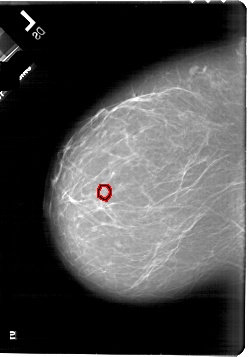

A_1818_1.LEFT_MLO

LEFT_MLO LINES 6676 PIXELS_PER_LINE 5116 BITS_PER_PIXEL 12 RESOLUTION 43.5 OVERLAY

FILE: A_1818_1.LEFT_MLO.OVERLAY

TOTAL_ABNORMALITIES 1

ABNORMALITY 1

LESION_TYPE CALCIFICATION TYPE PLEOMORPHIC DISTRIBUTION CLUSTERED

ASSESSMENT 4

SUBTLETY 1

PATHOLOGY BENIGN

TOTAL_OUTLINES 1

BOUNDARY